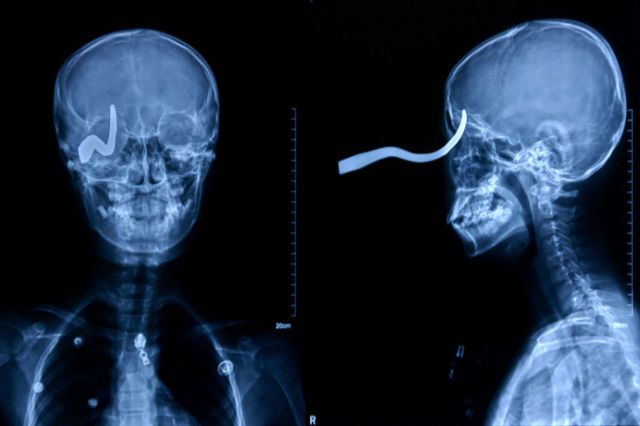

Eleven-year-old Chinese schoolboy Liu Cheong had a brush with death when his friend shot him in the head with a 16-inch arrow, according to numerous international media reports. The arrow entered his skull through the eye socket and lodged in the back of his head. Somehow, the boy was spared a fatal brain injury.

This X-ray shows how, during a fall, a car key penetrated the eyelid of 17-month-old Nicholas Holderman of Kentucky, reaching his brain. While doctors initially believed that the object had ruptured Nicholas' eyeball, another team of specialists later confirmed that the boy had sustained no permanent damage.

A 13-year-old slipped on an icy school floor in China. Xiao Lin fell forward onto a hook which embedded in his eye. A school handyman sawed the hook off the wall to free the lad, leaving 5cm sticking out of his head. Surgeon Yan Shijun commented: "The hook pierced his skull but was turned to the side by the impact. Any movement would have sent it into his brain and he could have died on the spot." He added: "He has lost his right eye but he's very lucky to be alive at all"

Wu Moude, 22, landed on a steel bar which penetrated 15cm into his head from beneath his chin. It took five hours of surgery to remove the bar, which saw surgeons cut open Wu's windpipe and skull.